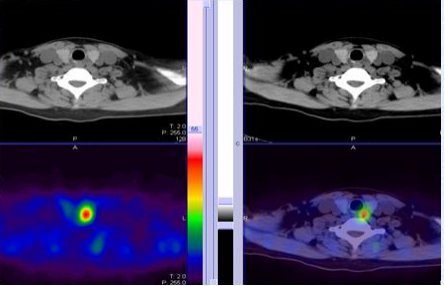

甲状旁腺的SPCET/CT融合显像(即核素 MIBI 显像与 CT 显像的融合)是代谢的和解剖的影像结合,能够对继发性甲状旁腺功能亢进症(SPTH)患者的甲状旁腺结节进行手术前精确定位。SPECT可提高甲状旁腺亢进结节检出的敏感度并能提供更精确的定位,SPECT/CT(图5):它能提供解剖和功能的融合图像。

图5 甲状旁腺增生的SPECT/CT融合图像